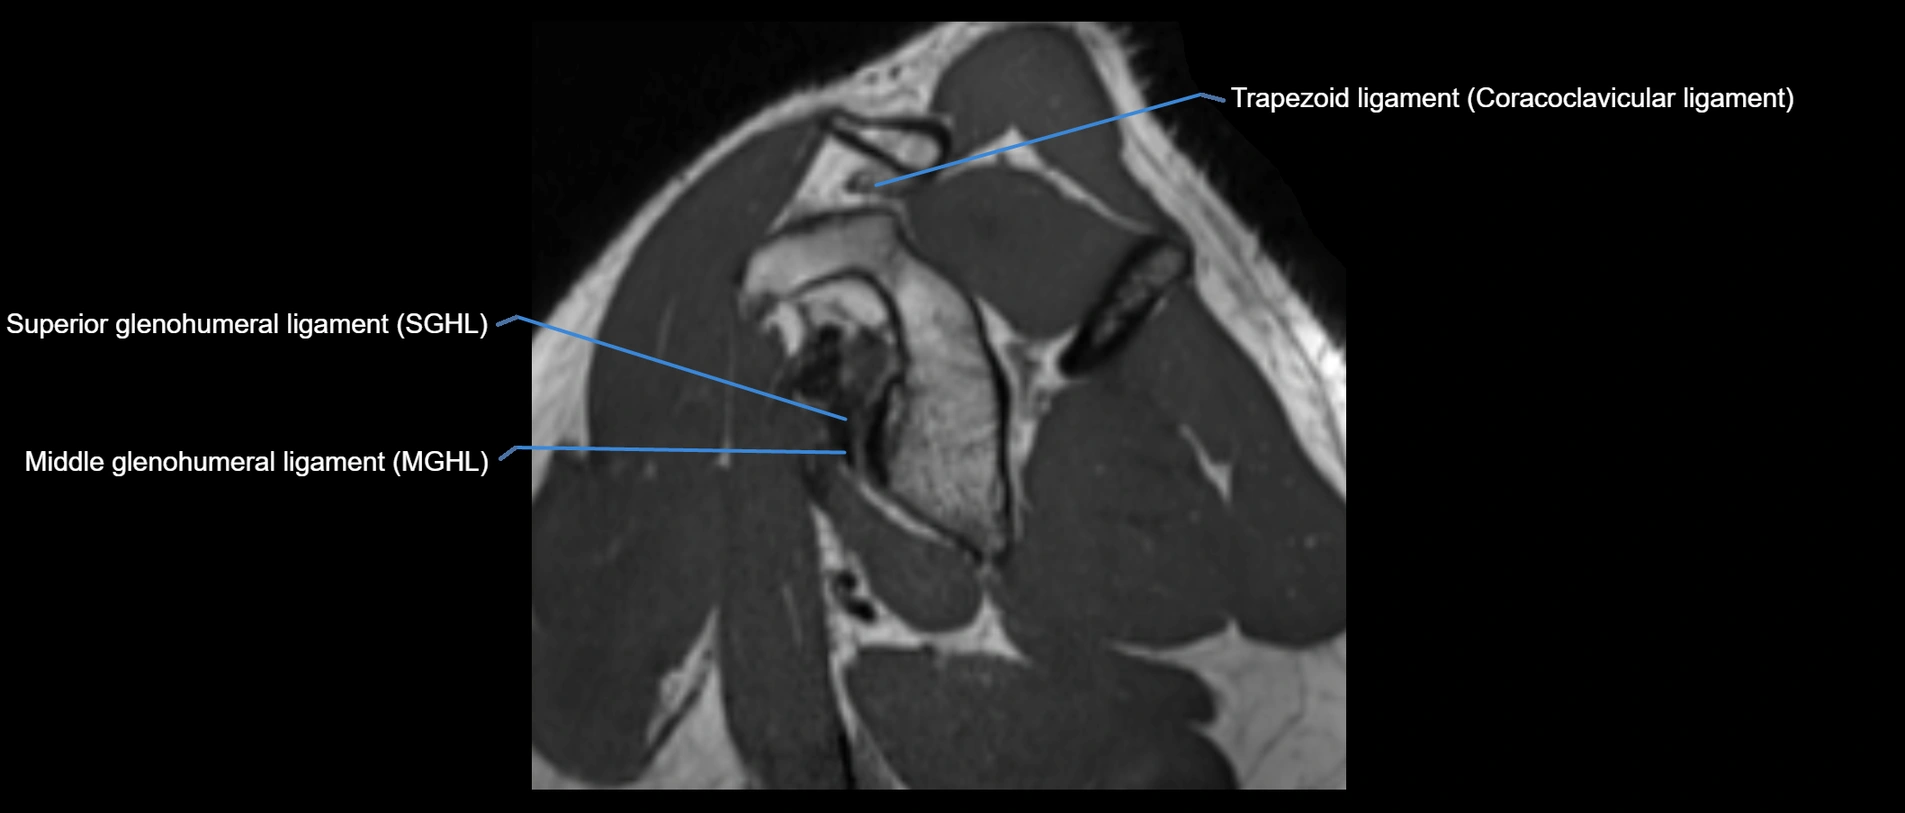

MRI images

image